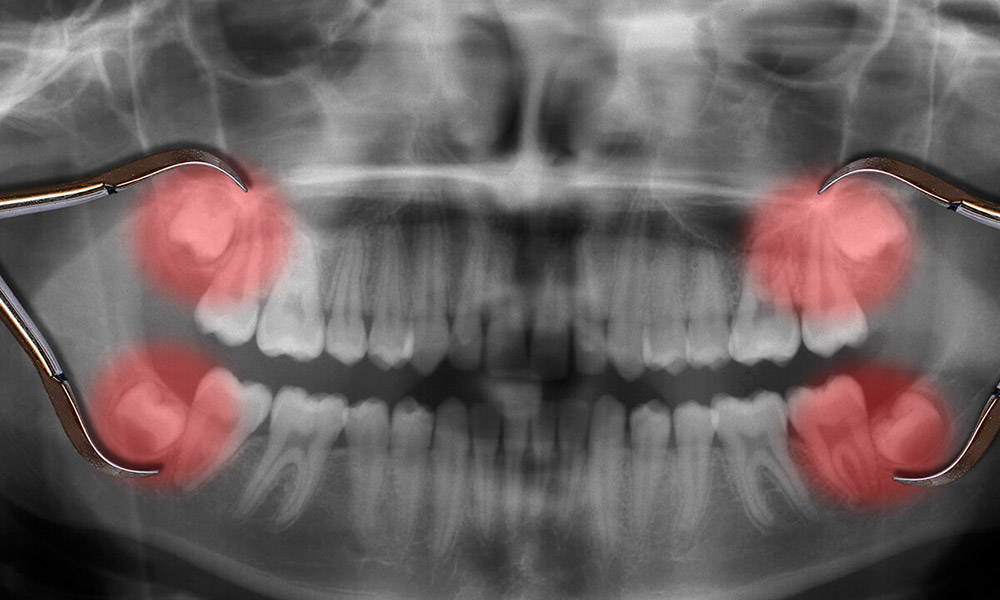

دندان عقل نهفته

دندان عقل نهفته دندانی است که فضای کافی برای رشد مناسب ندارد. ممکن است به صورت جانبی رشد کند، به سمت یا دور از دندانهای دیگر رشد کند، یا زیر خط لثه شما گیر کند.

دندان عقل نهفته میتواند باعث درد، تورم، عفونت و آسیب به دندانهای مجاور شود.

فشردگی یا نامرتبی

اگر دندان عقل فضای کافی برای بیرون آمدن نداشته باشد، میتواند به دندانهای دیگر فشار وارد کند و باعث شلوغی یا جابجایی شود. این میتواند بر روی گاز گرفتن شما تأثیر بگذارد و جویدن را دشوار کند.

اگر دندان عقل شما احتمالاً دندانهای شما را نامرتب میکند یا در کار ارتودنسی اختلال ایجاد میکند، دندانپزشک ممکن است کشیدن دندان عقل را پیشنهاد کند.

به هم ریختگی ساختار دندان ها بر اثر باقی ماندن دندان عقل

- از طریق عکس رادیولوژی، موقعیت نامناسب دندان تشخیص داده شود